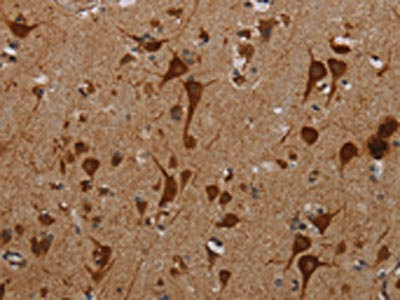

The image on the left is immunohistochemistry of paraffin-embedded Human brain tissue using CSB-PA965267(KMT2D Antibody) at dilution 1/40, on the right is treated with synthetic peptide. (Original magnification: ×200)

| CSB-PA965267 | KMT2D Antibody | Human | ELISA,IHC |